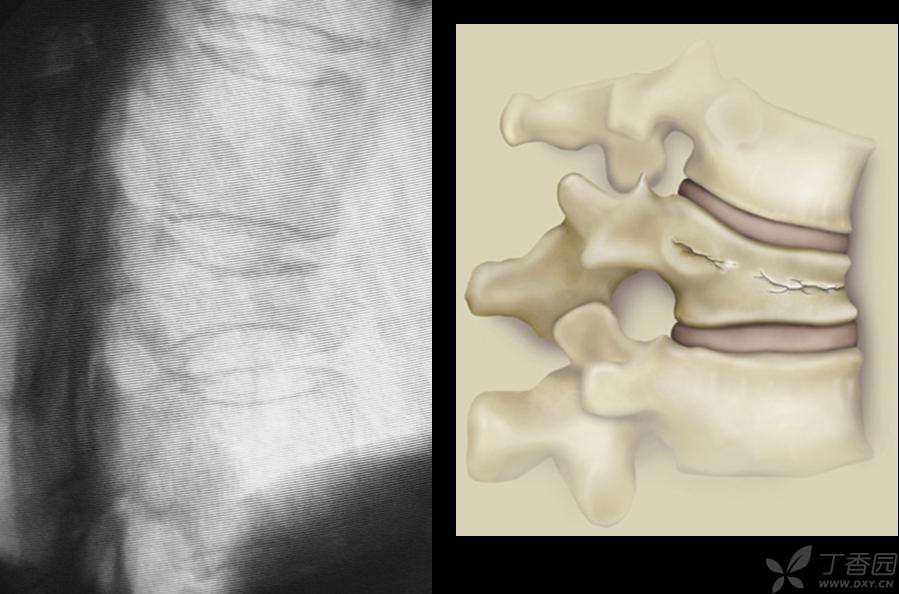

椎体压缩性骨折是患有骨质疏松症的老年人常见并发症之一,其总发病率约为2.04%,绝经后女性发病率更高,可达3.48%。

在椎体压缩性骨折中,1/3以上的患者表现为慢性顽固性疼痛。该病引起的疼痛、脊柱畸形可使患者肺活量下降、食欲减退、活动量减少,从而导致骨量进一步丢失,骨量的丢失又会造成椎体强度进一步下降,使其更易发生骨折,结果形成恶性循环。

球囊扩张最直接的优点,就是能够对病灶进行准确控制,传统的非球囊扩张椎体成形术不用球囊扩张直接将骨水泥注入压缩的椎体,由于骨水泥具有流体性质,会向压力较低的方向流动,因而有流入椎管压迫脊髓造成患者截瘫的可能,甚至可能流入椎旁静脉,导致更为危险的血管栓塞发生。球囊扩张椎体后凸成形术是通过球囊在椎体内挤压,使椎体复位,再注入骨水泥。这样就不会产生骨水泥外溢的副作用,因此具有安全、可靠、疗效确切、并发症少的优点。球囊扩张技术主要适用于治疗骨质疏松性椎体压缩性骨折,尤其是经过保守治疗无效或疼痛加重的情况,还有就是不宜长期卧床者,但是椎体严重压缩不能插入导针和注入骨水泥,或者椎体后缘破坏,脊髓受压等情况。该技术主要适用于胸5至腰5之间的椎体骨折,它可以分为经椎弓根和经椎弓根外两个手术途径进行操作。前者适用于胸10和腰5之间的椎体骨折,对病变范围在X线下定位后,经椎弓根进行准确的穿刺进入椎体、扩张球囊,使压缩的椎体膨胀形成一个四壁坚实的“球”状囊腔,然后将球囊取出来,在形成了一个空间的椎体中,放入骨水泥即可。后者适用于胸5~10之间椎体的骨折,因为胸椎椎弓根向内的倾斜角度很小,如果采用前者的方法则可能因置入的球囊太偏外侧而使椎体侧方皮质破裂,采用经椎弓外的方法,穿刺针经过椎弓根与肋骨之间进入椎体,就可以使穿刺针有足够的向内侧的倾斜度,使球囊置入较为理想的位置。

球囊扩张可以有效地纠正脊柱后凸畸形和恢复压缩椎体的正常高度,缓解和消除疼痛,而且不需做大切口手术,患者术后即可以活动,可以避免长期卧床可能导致的并发症。